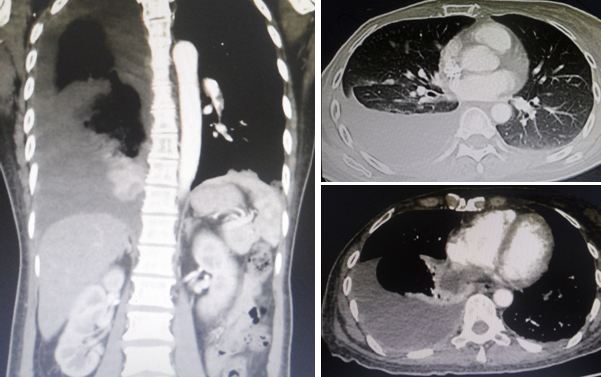

Ria came back to the same private hospital in Penang where she had her surgery. She was referred to the lung specialist. A CT was done and showed the following:

- There is a 5.5 x 5.1 x 3.5 cm mass in the manubrium sterni with an extension of the mass into the prevascular space of the mediastinum.

- There is moderate to large right pleural effusion (fluid in the lung).

- Collapse-consolidation of right lower lobe.

- Right and left main pulmonary arteries and their lobar branches are consistent with pulmonary embolism (PE).

From the pictures above, her breast cancer must have spread to her lungs, bone and liver. In addition she suffered DVT of the right leg. The doctor wanted Ria to be admitted into the hospital right away, to treat her DVT. She also refused.